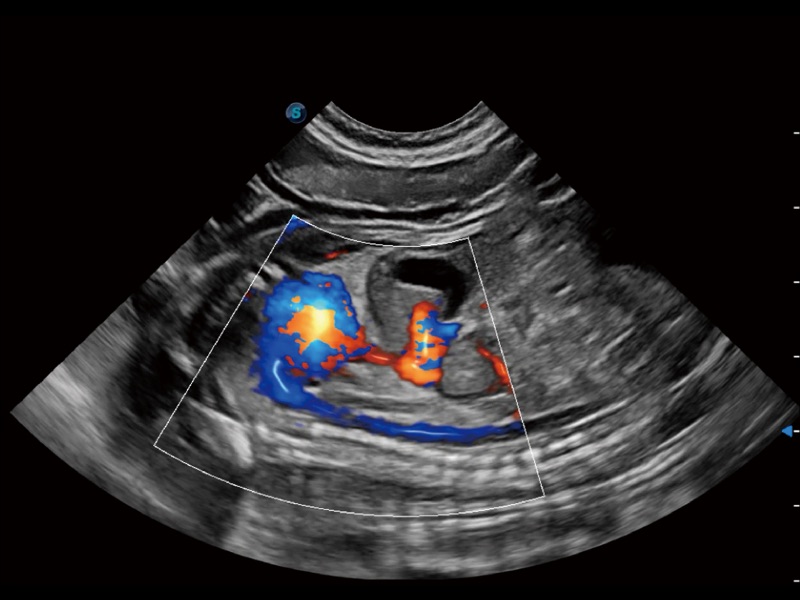

通過(guò)創(chuàng)新的 Matrix E自適應(yīng)濾波器和超長(zhǎng)時(shí)間域算法,極大提升超低速微細(xì)血流的檢出能力,同時(shí)更精準(zhǔn)地濾除軟組織和噪聲信號(hào),為獸用醫(yī)生提供以往無(wú)法通過(guò)常規(guī)血流獲得的疾病診斷信息。

通過(guò)色彩血流和實(shí)時(shí)寬景相結(jié)合,可觀(guān)察到完整的靜脈或動(dòng)脈的血流,方便醫(yī)生檢查。實(shí)時(shí)掃查過(guò)程中,如有任何操作失誤也可以很容易地進(jìn)行回掃擦除,而不會(huì)中斷掃查。